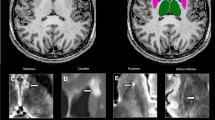

A summary of image post-processing and analysis steps is shown in Fig. 1.

Volumetric segmentation of dGM structures in FreeSurfer

The volumetric segmentations of dGM structures were performed with the FreeSurfer image analysis suite [17,18,19]. The dGM in each hemisphere was segmented into seven subcortical structures (caudate nucleus (CN), putamen (PT), globus pallidus (GP), thalamus (TH), hippocampus, amygdala, and nucleus accumbens) followed by the calculation of their volumes, which were then normalized to the estimated total intracranial volume (eTICV) to account for differences in individual brain sizes. The segmented dGM structures were mapped (converted) from the conformed FreeSurfer space to the native anatomical space “rawavg” space, thresholded (using the structure’s label value provided in the FreeSurfer’s look-up-table (LUT)), and binarized to extract the corresponding anatomy from the filtered phase, iron, T1, and MTR maps.